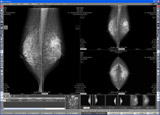

Infinet-Mammo

スクリーンショット

株式会社クライムメディカルシステムズは、超高解像度対応 マンモグラフィ専用画像診断ワークステーション「Infinet-Mammo 〜mammary〜」を2007年12月より出荷する